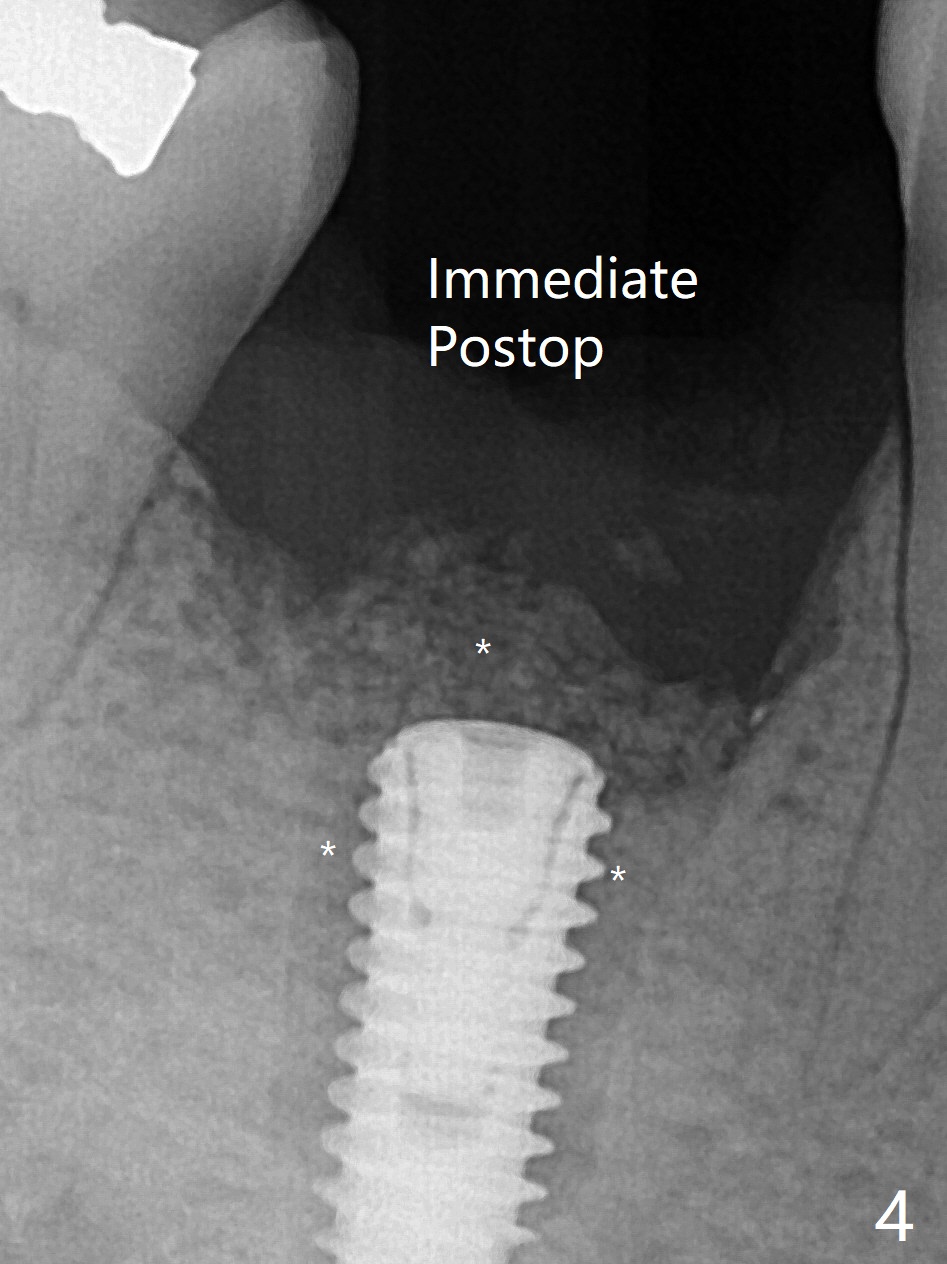

When the woman with periimplantitis at #30 returns to clinic, the abutment is found to be fractured (Fig.1 *) and difficult to remove. After implant removal with trephine burs, osteotomy is initiated lingual (Fig.2). A smaller and shorter implant (4.5x11.5 vs. 5.0x13 mm previously) is placed deeper (Fig.3) so that there is space for sticky bone buccal and coronal (Fig.4 *, 5 (postop reanalysis of preop CT)). After placement of 2 pieces of PRF membranes, the wound is closed with 4/0 PGA. The buccal flap is perforated due to periimplantitis and surgical manipulation. Periodontal dressing is applied.